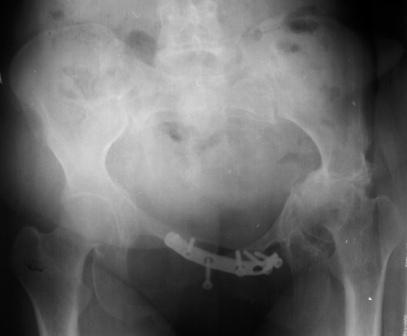

Уважаемые коллеги! Пациентка 32 года с застарелым повреждением таза, после остеосинеза лонного сочленения пластиной. Посоветуйте с выбором тактики и методик лечения.

Получила травму в феврале 2004г в г.Лобытнанги ЯНАО Тюм.обл. Через неделю после поступления выполнен остеосинтез лонного сочленения пластиной. 1,5 месяца на скелетном вытяжении. В последующем ходит при помощи костылей с нагрузкой на правую ногу. Имеется нестабильность половин таза, неправильно-консолидированный перелом левой вертлужной впадины, невропатия седалищного нерва слева. В результате невропатии седалищного нерва сформировалась эквинусная установка левой стопы, парестезии по подошвенной поверхности.

Направлена к нам для устранения патологической установки стопы и эндопротезирования левого тазобедренного сустава, также имеется миграция шурупов пластины, фиксирующей лонное сочленение.

Клинически: ходит на костылях с нагрузкой на правую ногу. Левая стопа в эквинусе. Осевая нагрузка на левую н\конечность болезненна в области левого тазобедренного сустава, при прикосновениях к подошвенной поверхности стопы у пациентки чувство зжения. В левом коленном суставе полный обьем движений, в левом тазобедренном резко ограничено отведение и ротация, укорочение левой н\конечности на 2,5 см. При полипроекционной и функциональной Р-графии выявлена нестабильность левого КПС и лонного сочленения, консолидированный в порочном положении поперечный оскольчатый перелом левой вертлужной впадины с центральным смещением головки бедра. Нами выполнена коррекция деформации левой стопы. Планируется выполнить введение 2 канюлированных илиосакральных винтов слева, реостеосинтез лонного сочленения реконструктивной пластиной, после заживления ран - тотальное эндопротезирование левого тазобедренного сустава.